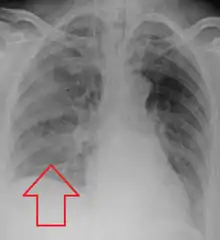

Location

Aspiration pneumonia is typically diagnosed by a combination of clinical circumstances (people with risk factors for aspiration) and radiologic findings (an infiltrate in the proper location).[1] A chest x-ray is typically performed in cases where any pneumonia is suspected, including aspiration pneumonia.[18] Findings on chest x-ray supportive of aspiration pneumonia include localized consolidation depending on the patient's position when the aspiration occurred.[19] For example, people that are supine when they aspirate often develop consolidation in the right lower lobe of the lung.[19] Sputum cultures are not used for diagnosing aspiration pneumonia because of the high risk of contamination.[20] Clinical symptoms may also increase suspicion of aspiration pneumonia, including new difficulty breathing and fever after an aspiration event.[6] Likewise, physical exam findings such as altered breath sounds heard in the affected lung fields may also be suggestive of aspiration pneumonia.[6] Some cases of aspiration pneumonia are caused by aspiration of food particles or other particulate substances like pill fragments; these can be diagnosed by pathologists on lung biopsy specimens.[21]